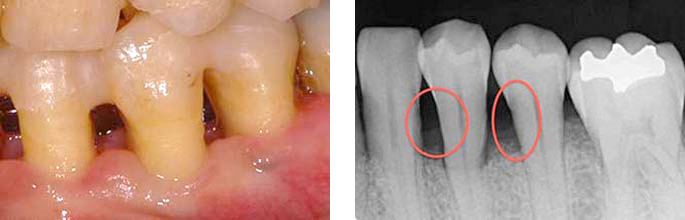

左下:全ての歯に多くの茶色い歯石が付着している、歯石で歯と歯の間が埋まっていることから歯槽骨の喪失も疑われます。

右下:歯石除去をし、歯肉の炎症がとれ引き締まった状態、結果的に治癒とともに歯と歯の間の歯茎の隙間が生じています。

写真では見えている歯石しか確認できませんが、レントゲンを取ってみると歯肉で見えない部分まで歯石が付いているのがわかります。

BEFORE(歯周基本治療前 レントゲン)

AFTER(歯周基本治療後 レントゲン)